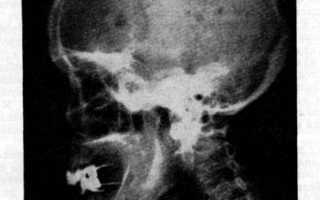

Рентгенограмма черепа при миеломе

Рентгенологическое исследование костей скелета (грудной клетки, таза, черепа, плечевой и бедренной кости, позвоночника) позволяет обнаружить в них очаги резорбции костной ткани и остеопороза. Про это следует помнить, что специфических рентгенологических признаков, характерных для миеломной болезни, не существует. Отсутствие остеодеструкций не исключает заболевания, а их наличие считается недостаточной для подтверждения диагноза.